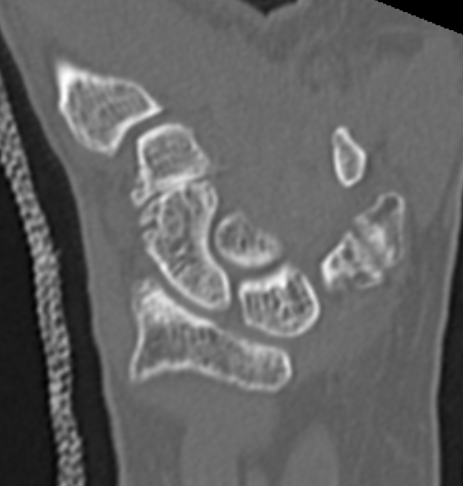

OA of the scapho-trapezium-trapezoidal (STT) joints

Third most common wrist osteoarthritis after CMC OA and SLAC wrist

- decorticate distal scaphoid / proximal trapezium / proximal trapezoid